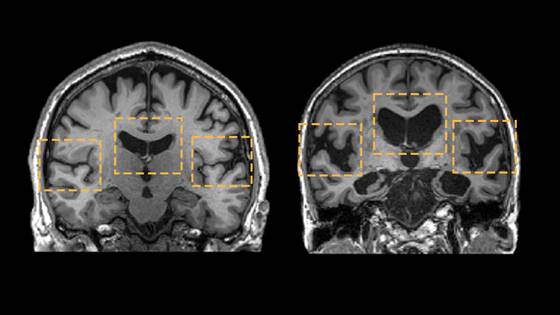

중년은 뇌 노화의 ‘가속 구간’이다. 연구들을 종합해 보면, 뇌는 나이에 따라 일정하게 늙지 않는다. 어떤 시기에는 완만하게, 어떤 시기에는 갑자기 확 꺾인다. 그 급격한 하강 구간이 바로 40대 전후다. 이때 해마와 백질 같은 핵심 부위의 부피가 빠르게 줄어들기 시작한다. 해마는 기억과 감정, 자아 정체성을 담당하는 곳이다. 이곳이 위축되면, 단순히 기억력이 나빠지는 걸 넘어 ‘내가 누구인지’에 대한 감각까지 흐려질 수 있다.

문제는, 이 모든 변화가 아무 경고 없이 시작된다는 점이다. 대부분의 사람은 60대가 돼서야 “뇌가 예전 같지 않다”고 느낀다. 하지만 그때는 이미 많은 변화가 되돌릴 수 없는 단계에 접어든 뒤다. 그래서 최근의 치매 연구는 노년이 아니라 중년의 뇌를 주목하기 시작했다.

이 시기에 어떤 선택을 하느냐에 따라, 뇌 노화는 완만해질 수도 있고 폭주할 수도 있다. 실제로 같은 나이, 같은 유전자를 가진 사람들 사이에서도 중년 이후부터 격차는 급격히 벌어진다. 누군가는 50대에도 또렷한 기억력과 판단력을 유지하는 반면, 누군가는 눈에 띄게 늙는다.